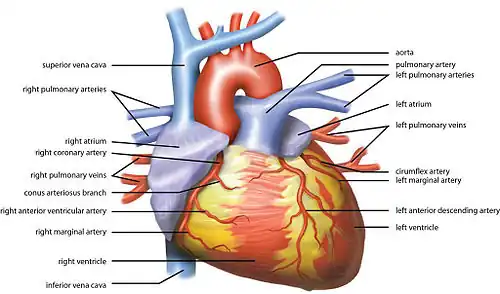

While heart rhythm is regulated entirely by the sinoatrial node under normal conditions, heart rate is regulated by sympathetic and parasympathetic input to the sinoatrial node. The accelerans nerve provides sympathetic input to the heart by releasing norepinephrine onto the cells of the sinoatrial node (SA node), and the vagus nerve provides parasympathetic input to the heart by releasing acetylcholine onto sinoatrial node cells. Therefore, stimulation of the accelerans nerve increases heart rate, while stimulation of the vagus nerve decreases it.[6]

The heart rate is rhythmically generated by the sinoatrial node. It is also influenced by central factors through sympathetic and parasympathetic nerves.[11] Nervous influence over the heart rate is centralized within the two paired cardiovascular centres of the medulla oblongata. The cardioaccelerator regions stimulate activity via sympathetic stimulation of the cardioaccelerator nerves, and the cardioinhibitory centers decrease heart activity via parasympathetic stimulation as one component of the vagus nerve. During rest, both centers provide slight stimulation to the heart, contributing to autonomic tone. This is a similar concept to tone in skeletal muscles. Normally, vagal stimulation predominates as, left unregulated, the SA node would initiate a sinus rhythm of approximately 100 bpm.[12]

Both sympathetic and parasympathetic stimuli flow through the paired cardiac plexus near the base of the heart. The cardioaccelerator center also sends additional fibers, forming the cardiac nerves via sympathetic ganglia (the cervical ganglia plus superior thoracic ganglia T1–T4) to both the SA and AV nodes, plus additional fibers to the atria and ventricles. The ventricles are more richly innervated by sympathetic fibers than parasympathetic fibers. Sympathetic stimulation causes the release of the neurotransmitter norepinephrine (also known as noradrenaline) at the neuromuscular junction of the cardiac nerves. This shortens the repolarization period, thus speeding the rate of depolarization and contraction, which results in an increased heartrate. It opens chemical or ligand-gated sodium and calcium ion channels, allowing an influx of positively charged ions.[12]

Norepinephrine binds to the beta–1 receptor. High blood pressure medications are used to block these receptors and so reduce the heart rate.[12]

Parasympathetic stimulation originates from the cardioinhibitory region of the brain[13] with impulses traveling via the vagus nerve (cranial nerve X). The vagus nerve sends branches to both the SA and AV nodes, and to portions of both the atria and ventricles. Parasympathetic stimulation releases the neurotransmitter acetylcholine (ACh) at the neuromuscular junction. ACh slows HR by opening chemical- or ligand-gated potassium ion channels to slow the rate of spontaneous depolarization, which extends repolarization and increases the time before the next spontaneous depolarization occurs. Without any nervous stimulation, the SA node would establish a sinus rhythm of approximately 100 bpm. Since resting rates are considerably less than this, it becomes evident that parasympathetic stimulation normally slows HR. This is similar to an individual driving a car with one foot on the brake pedal. To speed up, one need merely remove one's foot from the brake and let the engine increase speed. In the case of the heart, decreasing parasympathetic stimulation decreases the release of ACh, which allows HR to increase up to approximately 100 bpm. Any increases beyond this rate would require sympathetic stimulation.[12]